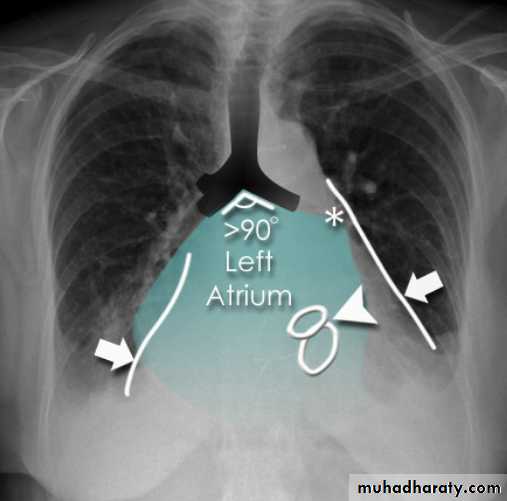

Radiographic featuresPlain film

Typical radiographic features of mitral regurgitation include :

frontal projection

1.left atrial enlargement

convexity or straightening of the left atrial appendage just below the main pulmonary artery (along left heart border)

2.double density sign: the right side of the enlarged left atrium pushes into the adjacent lung and creates an addition contour superimposed over the right heart

3.elevation of the left main bronchus and splaying of the carina

4.upper zone venous enlargement due to pulmonary venous hypertension

5.left ventricular enlargement is also eventually present due to volume overload

6.Features of pulmonary oedema may also be present.

Mitral valve disease